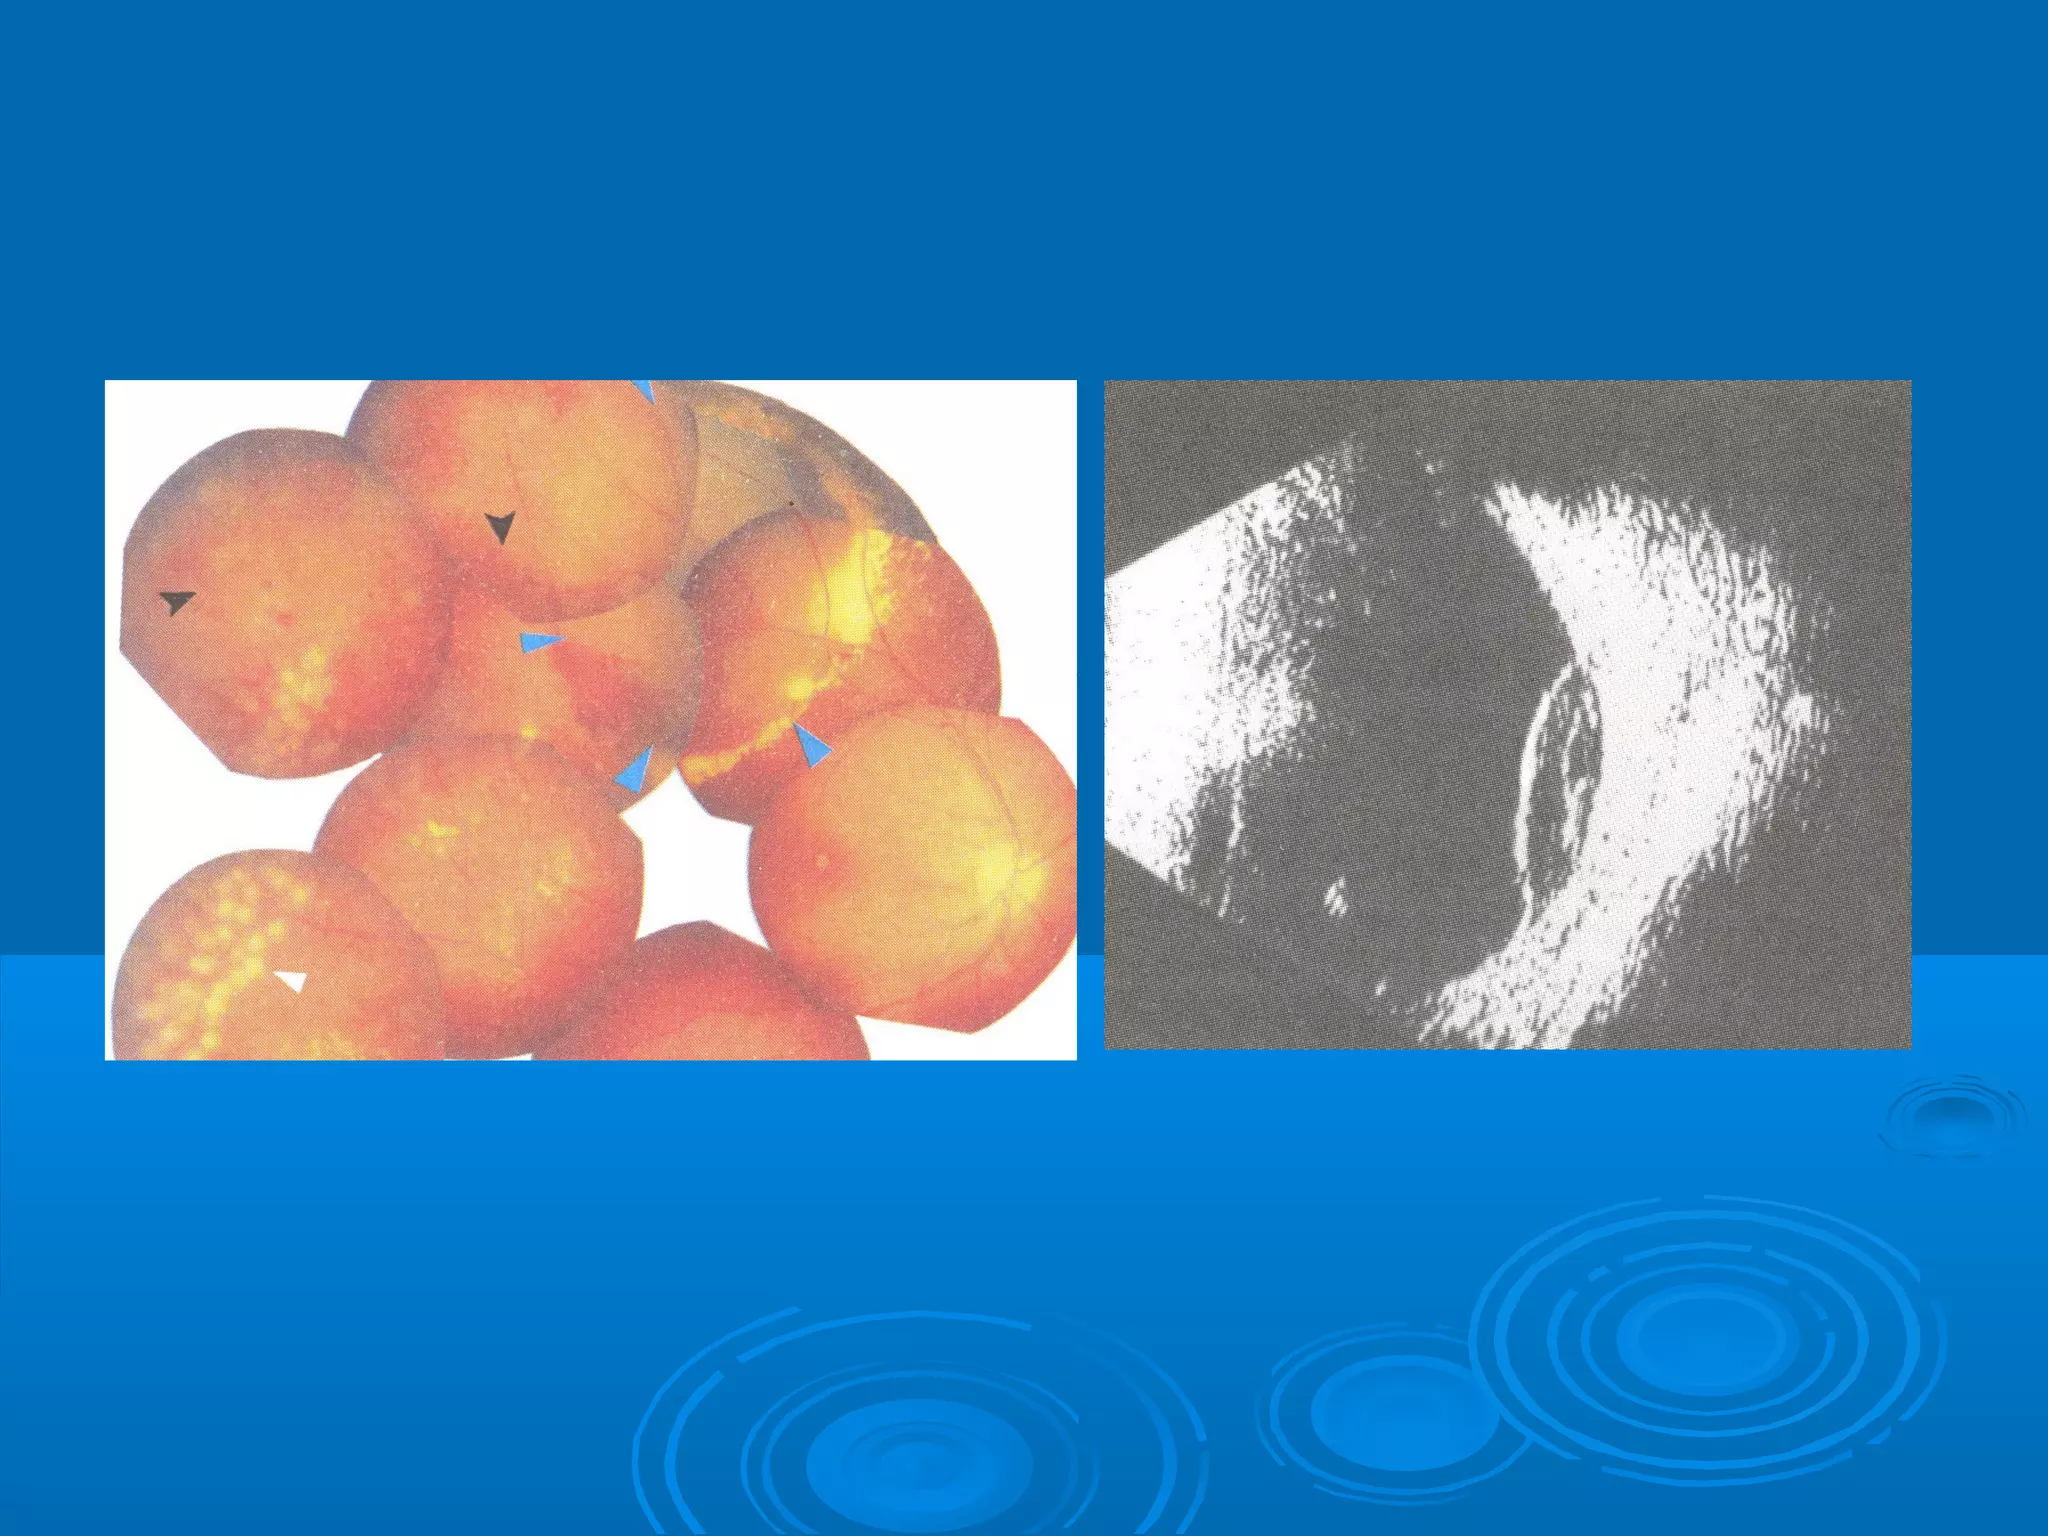

Болезнь Коатса - это идеопатическое заболевание, характеризующееся полиморфными изменениями сосудов сетчатки с массивной экссудацией, чаще всего у детей и подростков, с преобладанием среди мальчиков. Эпидемиология показывает, что заболевание проявляется, как правило, в возрасте 8-16 лет, но возможно его обнаружение и у взрослых. Основные проявления включают ретинальные аномалии, субретинальную экссудацию и постепенно прогрессирующую потерю зрения.